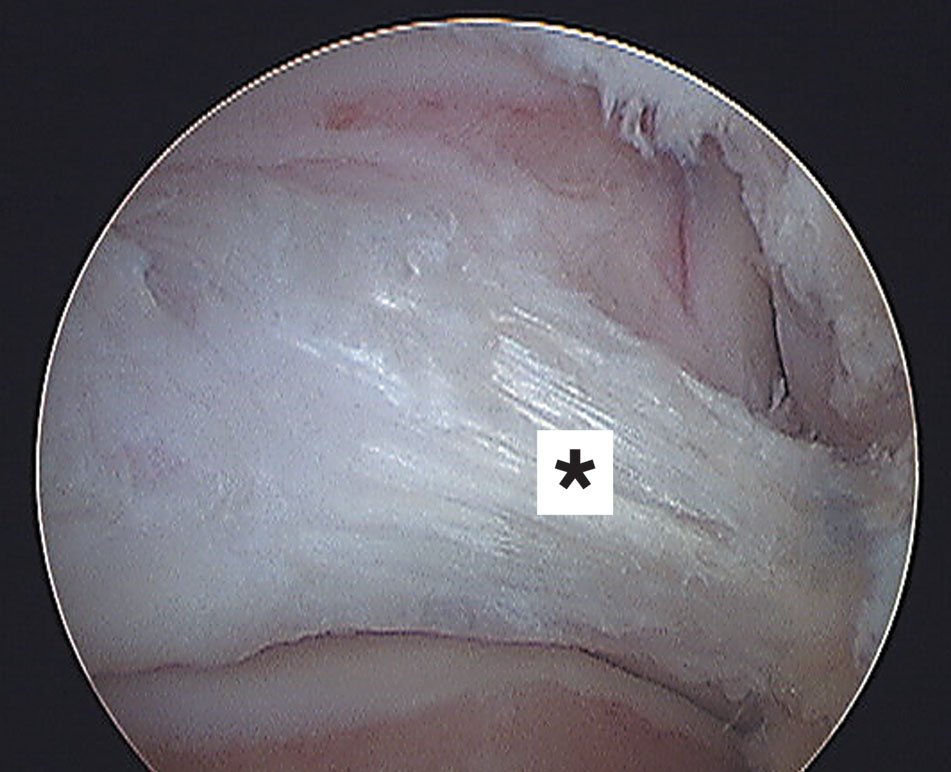

Figura 8: Vista artroscópica del ligamento intermaleolar posterior.

El ligamento talofibular posterior es un ligamento fuerte y grueso con forma trapezoidal localizado en un plano casi horizontal, tener en cuenta que es intracapsular y extrasinovial. Se origina en el maléolo lateral (fosa maleolar) y va hasta la parte lateral del astrágalo (Fig. 5). Es multifasicular por ese motivo sus fibras llegan: a la parte posterior del astrágalo y pueden llegar al tubérculo lateral del astrágalo, al os trigonum si está presente (Fig. 6), al proceso trigonal (Stieda) y otras contribuyen a formar el retináculo del tendón flexor largo del hallux (4) (Fig. 7). También llega hasta el componente profundo (ligamento transverso) del ligamento tibiofibular posterior y contribuye a formar el ligamento intermaleolar posterior, denominación propuesta por Paturet (8), también denominado “tibial slip” por Chen (9) y otros autores (Fig. 8, 9). Ayudando a formar el labrum existente en el margen posterior de la tibia.

Una causa de que su presencia según algunos autores no es constante (10) (11) (12) (13) puede ser se gún Golanó (3) al pequeño tamaño del ligamento (promedio 2.3 mm con un rango de 1 a 5 mm) y a la dificultad de disecarlo. Un 20 % se divide en dos a tres bandas (10). En una vista posterior se sitúa entre el ligamento transverso y el ligamento talofibular posterior y se dirige oblicuamente desde lateral a medial y de abajo a arriba. Se tensa en flexión dorsal y se relaja en flexión plantar. Al relajarse se puede interponer entre la tibia y el astrágalo provocando un síndrome friccional posterior de tobillo, acentuado si hay factores predisponentes como proceso trigonal (Stieda), os trigonum o proceso posterior prominente del os calcis (7).